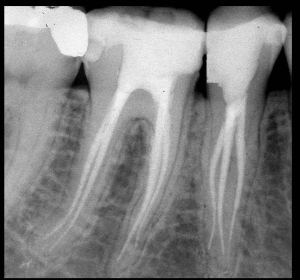

Radiografie Endorali: sono radiografie più dettagliate e specifiche che permettono di visualizzare 3/4 denti al massimo.

Esistono le cosiddette bitewing, radiografie particolari, indispensabili per valutare carie occlusali o interprossimali.

Poi ci sono le radiografie tradizionali che vengono utilizzate per valutare tasche ossee, l’allungamento dello spazio periodontale, la presenza di carie occlusali o inter prossimali, la presenza di granulomi apicali.

È inoltre uno strumento diagnostico di grande importanza per l’endodontista che se ne può avvalere nelle diverse fasi di terapia canalare per valutare la lunghezza presuntiva del canale radicolare, la lunghezza di lavoro strumentale, l’adeguata scelta del cono di chiusura, lo studio finale dopo compattamento del cono di guattaperca.